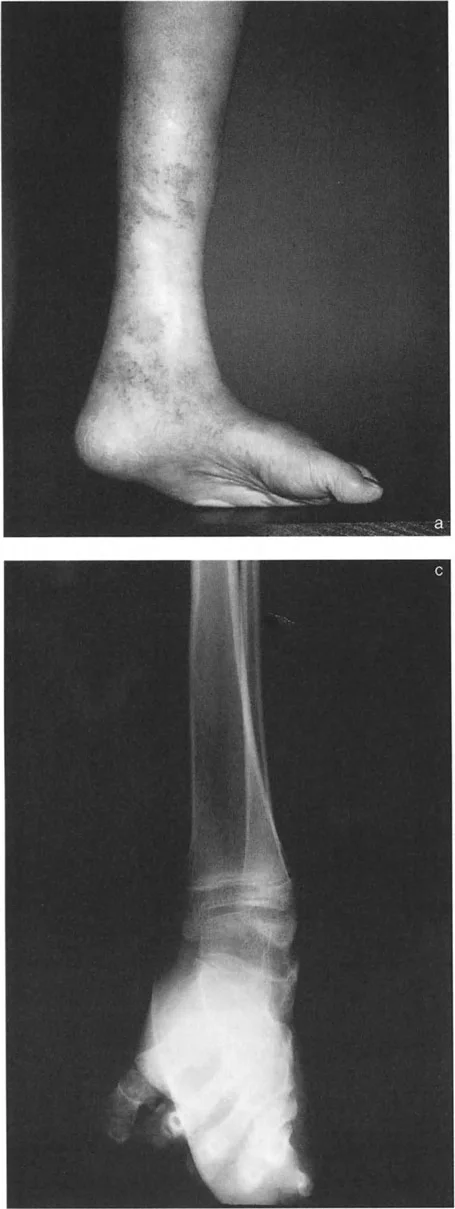

التصوير الإشعاعي المتقدم

التصوير الإشعاعي هو الأداة الأساسية لتأكيد التشخيص وتحديد تفاصيل التشوه.

* الأشعة السينية (X-rays) الواقفة لكامل الطرف السفلي: هذه الأشعة ضرورية لتقييم المحاذاة الكلية للطرف السفلي تحت تأثير وزن الجسم. يطلب الأستاذ الدكتور محمد هطيف صورًا شعاعية كاملة الطول للساق أثناء الوقوف (Full-length standing alignment films) لتقييم المحور الميكانيكي للساق وتحديد زوايا المفاصل بدقة.

* الأشعة السينية الجانبية والامامية الخلفية للكاحل: تُظهر هذه الصور تفاصيل مفصل الكاحل نفسه، بما في ذلك زاوية القصبة الأمامية البعيدة (ADTA) وزاوية القصبة الوحشية البعيدة (LDTA)، وهي زوايا حاسمة لتحديد التشوه في المستويين الأمامي والسهمي.

* منظر سولتزمان (Saltzman View): هذا المنظر الإشعاعي الخاص يتم الحصول عليه بزاوية 20 درجة لقياس محاذاة عظم العقب (Calcaneus) بالنسبة لقصبة الساق، وهو أمر بالغ الأهمية لتقييم تعويضات القدم الخلفية.

أنواع جراحات قطع العظم فوق الكاحل (Supramalleolar Osteotomy)

جراحة قطع العظم فوق الكاحل (SMO) هي الإجراء الأكثر شيوعًا لتصحيح تشوهات قصبة الساق البعيدة. تتضمن هذه الجراحة قطعًا دقيقًا في عظم الساق (القصبة) فوق مفصل الكاحل مباشرة، ثم إعادة محاذاة العظم وتثبيته في الوضع الصحيح. هناك عدة أنواع من هذه الجراحة: